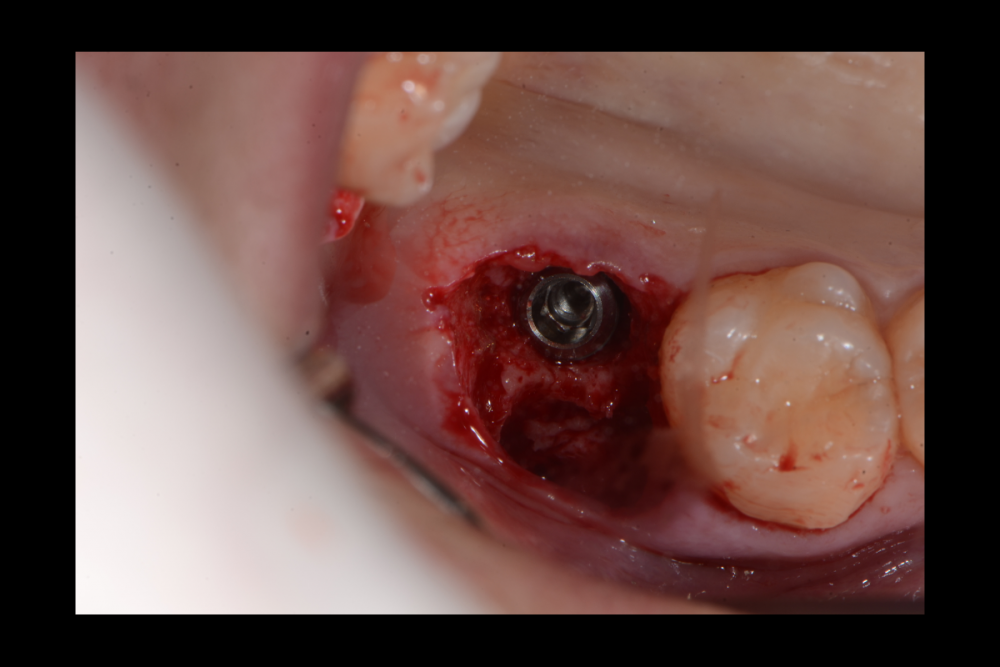

Карен Аванесов Опубликовано 20 сентября, 2021 Поделиться Опубликовано 20 сентября, 2021 (изменено) одномоментной установки имплантата, без вторжения в верхнечелюстной синус, регионарная мягкотканная пластика, выгодная ортопедическая ангуляция, не выгодной небной лунки. Пустоты заполнены губкой дигестол, дополнительная герметизация ликвидам. Мой только хирургический протокол, пациент реферативный. Время работы от удаления до имплантации 40 минут, ожидание до протезирования 3 месяца. Кейс посвящаю одноглазому и зеленому хулигану, любителю пива и девок, не знаю куда он делся, но пусть не грустит, все будет хорошо! Изменено 20 сентября, 2021 пользователем Карен Аванесов 10 1 1 Ссылка на комментарий

Карен Аванесов Опубликовано 25 сентября, 2021 Автор Поделиться Опубликовано 25 сентября, 2021 22.09.2021 в 18:52, сирена сказал: Ок) Бум ждать. А длина импланта какая? 10х4.5 1 Ссылка на комментарий